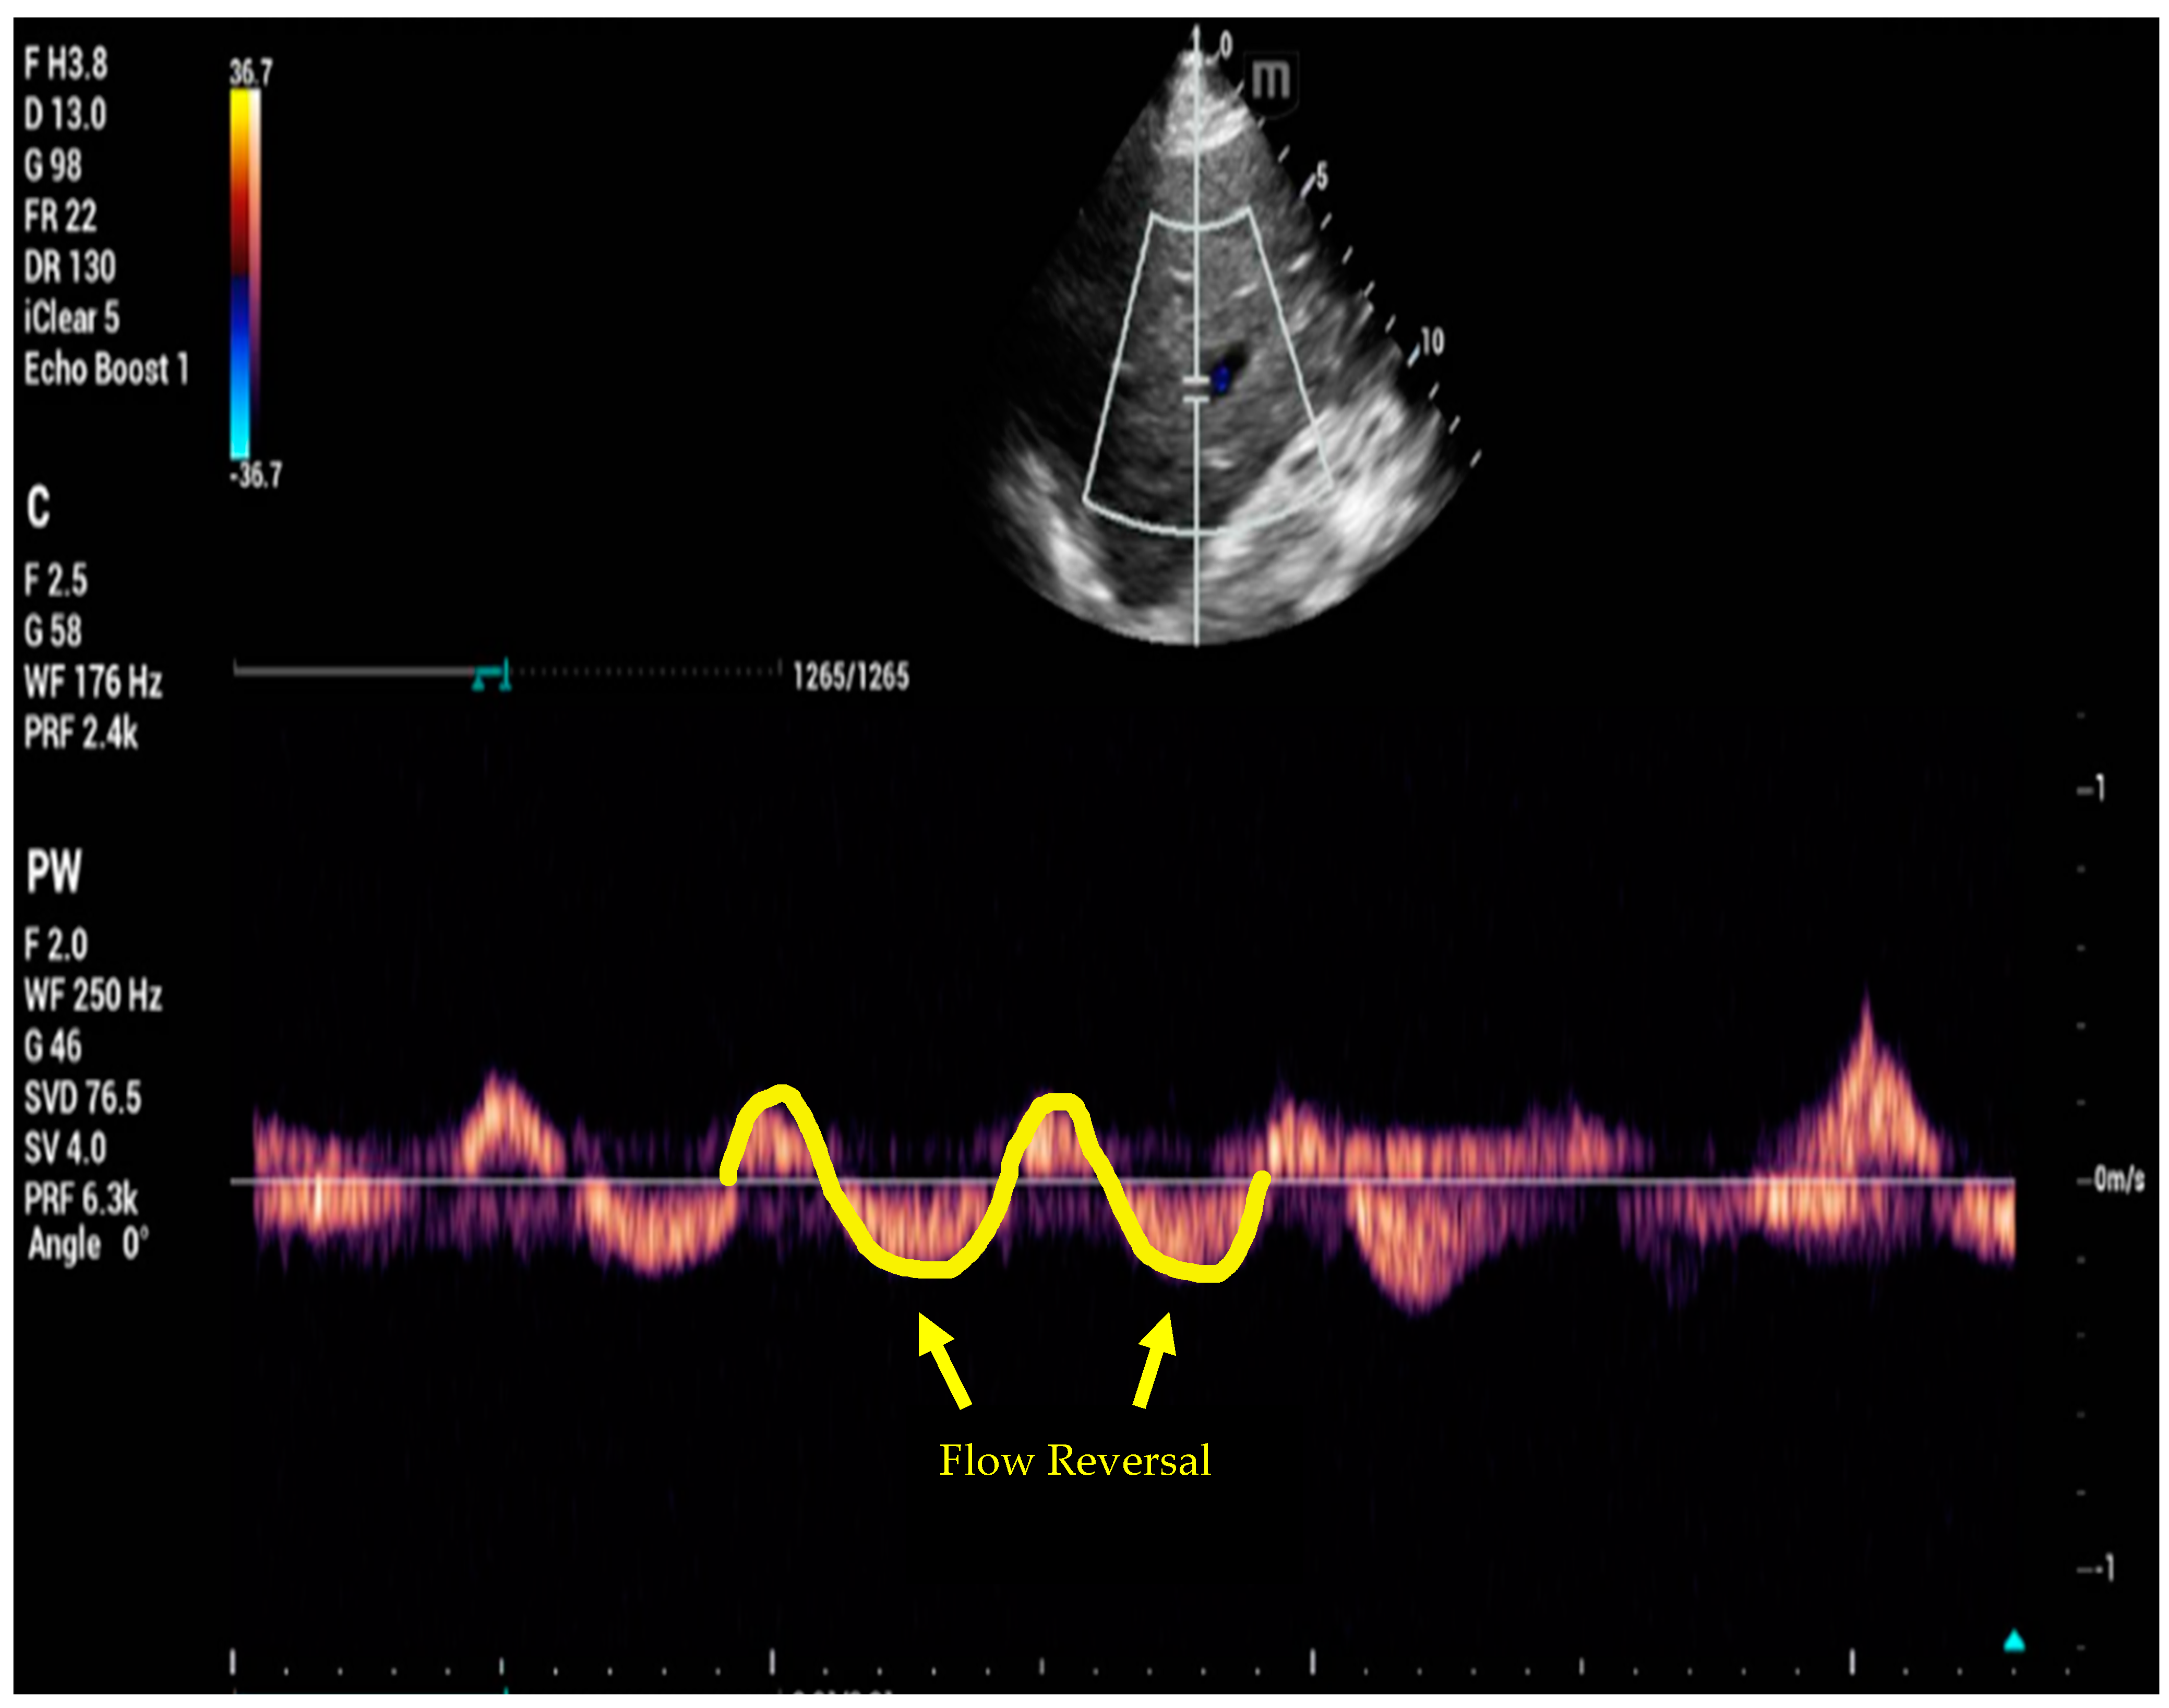

6. Venous Excess Ultrasound Score